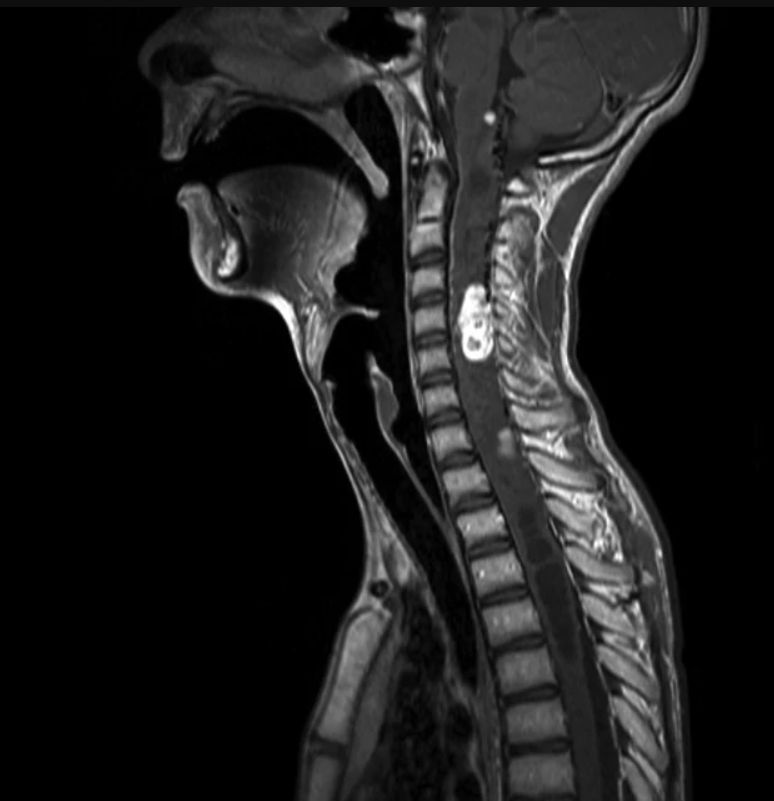

Εδώ οι πιθανότητες είναι 1 ανά 35.000 ανθρώπους. Η εξαιρετικά σπάνια γενετική ανωμαλία, μία μόνο από τις 7.000 γνωστές κληρονομικές διαταραχές, χαρακτηρίζεται από την ανάπτυξη όγκων σε διαφορετικά μέρη του σώματος, ακόμα και στο Κεντρικό Νευρικό Σύστημα, αν και οι νεοπλασίες είναι συνήθως καλοήθεις (αιμαγγειώματα στον εγκέφαλο, τη σπονδυλική στήλη και τον αμφιβληστροειδή).

Αναλόγως με τη θέση των νεοπλασιών, το αυτοσωμικό επικρατές γενετικό νόσημα VHL μπορεί να αποδειχθεί περισσότερο ή λιγότερο επικίνδυνο, ακόμα και θανατηφόρο, επιφέροντας εγκεφαλικά επεισόδια, εμφράγματα και αναπνευστικά προβλήματα…